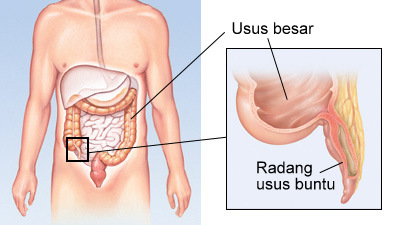

Artikel Kesehatan Mitra Keluarga Radang Usus Buntu

Artikel Kesehatan Mitra Keluarga Radang Usus Buntu

Cari Tahu Letak Dan Penyebab Usus Buntu

Cari Tahu Letak Dan Penyebab Usus Buntu